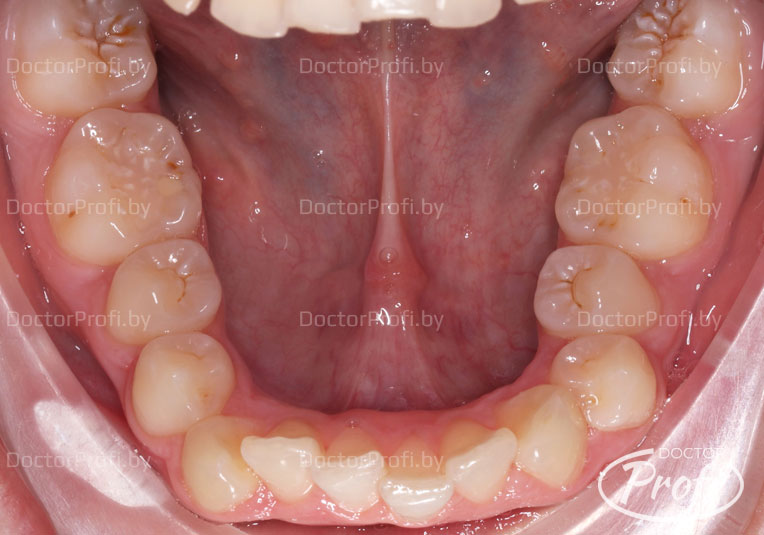

Пациентка обратилась в клинику с жалобами на неэстетичный зубной ряд. На консультации у ортодонта были выявлены следующие проблемы: глубокий прикус с сужением верхнего и нижнего зубных рядов, скученное положение резцов.

- Проведена коррекция прикуса. Исправлена форма зубных рядов и положение зубов.

В результате ортодонтического лечения пациентка обрела красивую улыбку, правильный прикус, ровные и здоровые зубы.